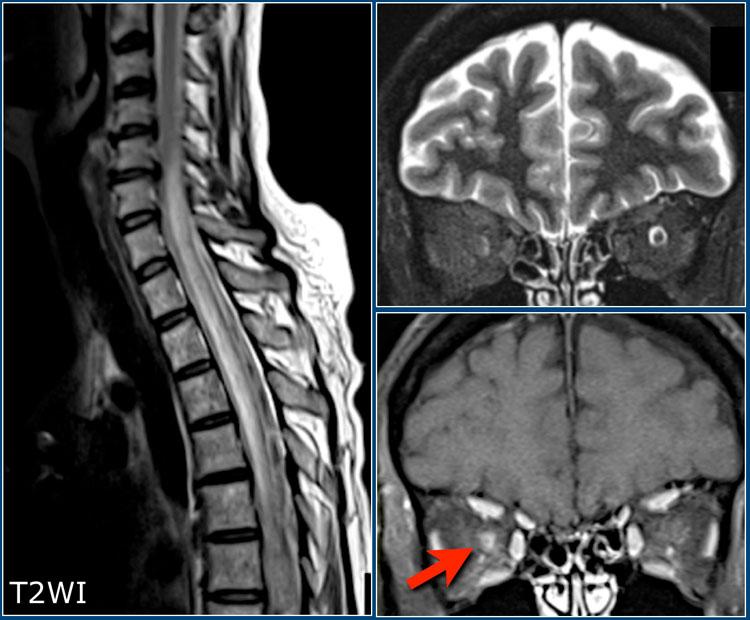

Tổn thương tủy sống

Các tổn thương tủy sống điển hình trong MS thường có kích thước tương đối nhỏ và nằm ở vị trí ngoại vi.

Chúng thường gặp nhất ở đoạn tủy cổ và thường có chiều dài dưới 2 đốt sống.

Tổn thương tủy sống kết hợp với tổn thương ở tiểu não hoặc thân não rất gợi ý chẩn đoán MS.

Tổn thương tủy sống ít gặp trong hầu hết các bệnh lý thần kinh trung ương khác, ngoại trừ ADEM, sarcoidosis và NMOSD.

Các hình ảnh cho thấy nhiều tổn thương đoạn ngắn trong tủy sống.

Trên chuỗi xung mật độ proton (PDW), tủy sống có tín hiệu thấp đồng nhất (tương tự dịch não tủy – CSF), tạo ra độ tương phản tốt giữa các tổn thương MS với dịch não tủy xung quanh và mô tủy bình thường.

Sử dụng ma trận 512 và kỹ thuật đồng bộ tim (cardiac gating) để đạt kết quả tối ưu.

Chuỗi xung STIR là một lựa chọn thay thế tốt cho PDW.

Cần đảm bảo có hai chuỗi xung khác nhau hoặc hai mặt phẳng chụp khác nhau.